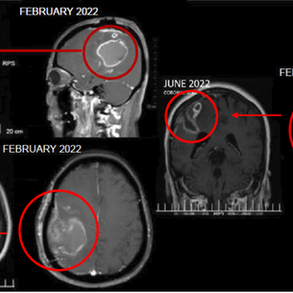

At some point, I understood that I needed more support. I contacted the ECCT team, and they explained to me how ECCT works. During the initial consultation, the team carefully reviewed my medical history, imaging, biopsy results, and symptoms. They encourage me to get proper biopsy and told me that it is likely recurrent of metastatic TNBC. The scan later on does confirm it’s TNBC involving my liver, bone, lung, and lymph nodes. The biopsy as well confirmed a highly aggressive recurrence. The tumour was again triple-negative, now with a Ki-67 of 90%, extensive necrosis, numerous atypical mitoses, and no PD-L1 expression, these features associated with fast growth and limited immunotherapy options.

By December 2025, PET-CT imaging showed a clear and significant treatment response for my resolution of TNBC Ki-67 of 90%:

– Liver metastases had markedly reduced in size and metabolic activity

– Bone lesions were less active

– Lung nodules showed improvement

– The ulcerated breast tumour had become significantly smaller

This gave me a lot of hope. It confirmed what I do is heading to the right direction.